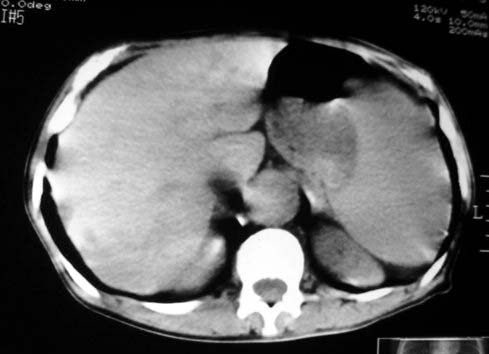

以下是引用dyqct在2007-4-20 16:38:00的发言:[br]考虑:1、巨脾;[br] 2、肝内多发低密度,首先考虑转移瘤;[br] 3、胆囊多发结石。

以下是引用andymaomao在2007-4-20 16:47:00的发言:[br]肝脾增大,肝内胆管扩张,且可见多发小囊性低密度灶,胆囊窝区高密度影,手术化疗病史,贫血....[br]1.肝脾大及贫血与术后化、药疗有关;[br]2.胆囊窝区高密度影,术后改变?肝内胆管扩张,积液?[br]3.肝内多发低密度灶,性质?建交增强